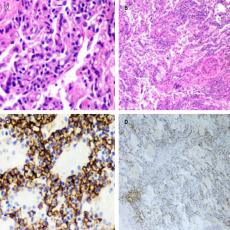

Síndrome de fuga aérea torácica por enfermedad de injerto contra huésped posterior a trasplante alogénico de médula ósea

Montero-Ureña, Raúl Enrique1; Contreras-Rodríguez, Felipe de Jesús2; Márquez-Barajas, Jesús1; Anaya-Gómez, Francisco José1; García-González, Luis Alberto1; Valdez-Rojas, Leonora1; Garnica-Vázquez, Johana Jazer1; Jiménez-Tornero, Jorge1; Díaz-Alba, Alexandra1; Luna-González, Cristina Alejandra1; Álvarez-González, Martha Georgina1; García-Valadez, Yunuen1; Solano-Genesta, Manuel1